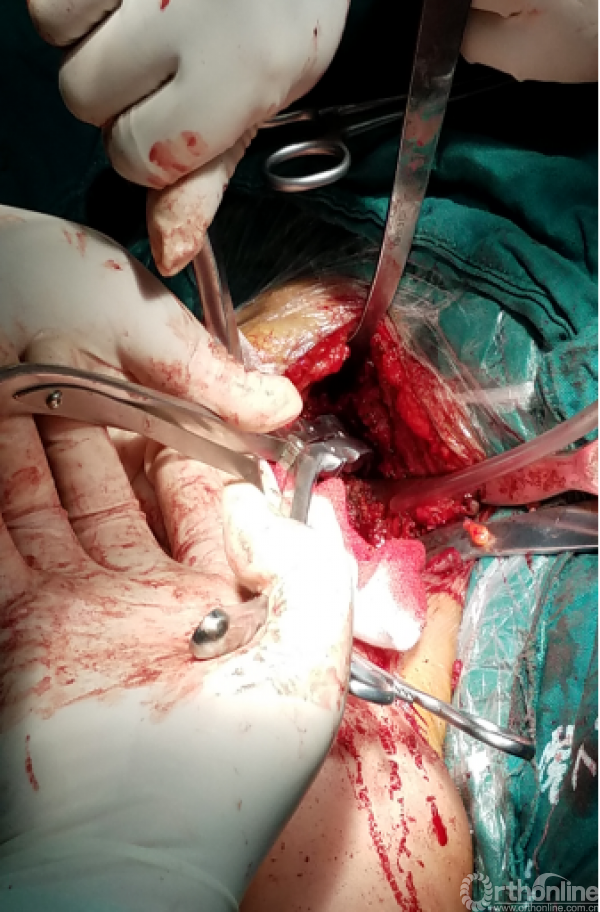

1.抗生素骨水泥占位器植入

2.不锈钢克氏针+抗生素骨水泥

3.柄部没有骨水泥,利于引流,头部较原有假体头部偏大,减少挛缩,占位关节腔,颈干角及后倾维持

4.用肌腱缝线固定减少排斥

5.后内侧结构尽量不去干扰,防止出现神经血管损伤。

术后X线